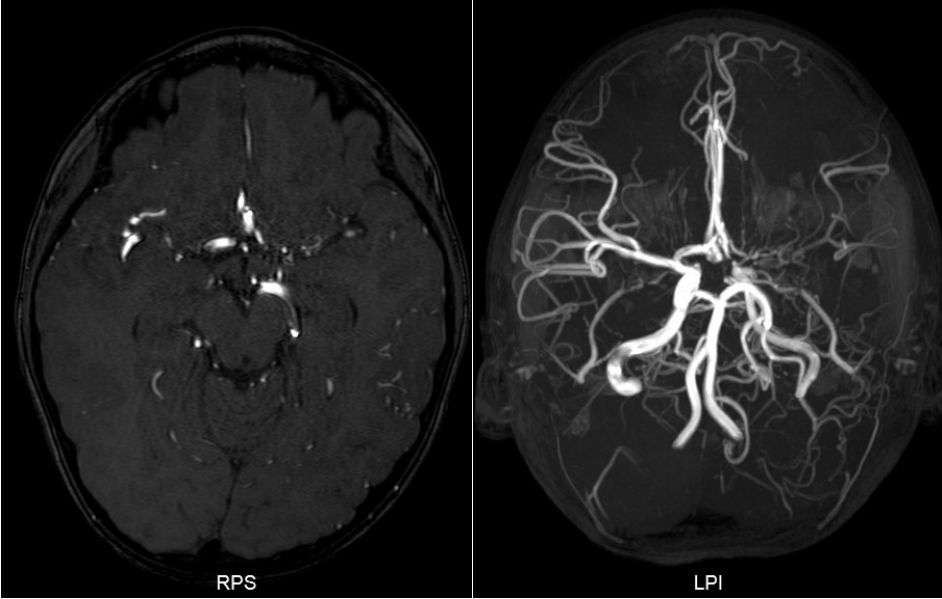

查头颅MRI提示:左侧鞍上可见两处结节状异常信号影,病变内信号不均匀,周围可见扭曲血管流空影,增强后明显强化,血管畸形伴出血可能(图2)。

![]()

图2. MRI提示鞍上及外侧裂区多发类圆形结节病灶,强化明显,边界清。